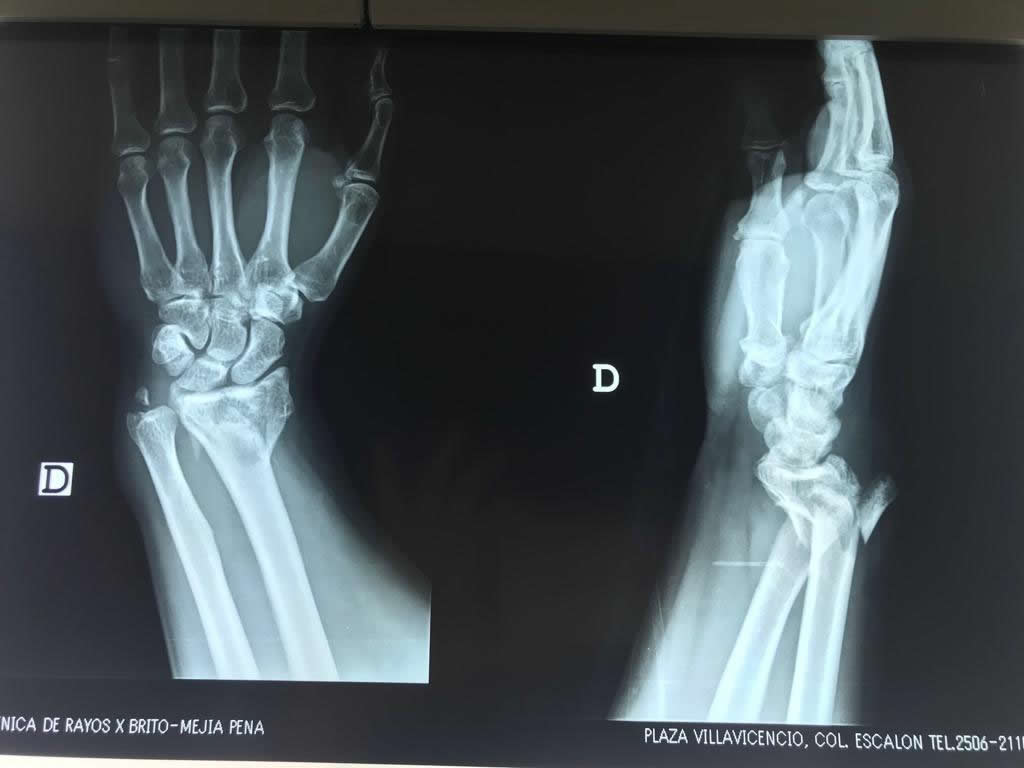

Calcaneo - Cirugías de Muñecas y Manos

Los procedimientos más comunes en cirugía de la mano son aquellos destinados a reparar traumatismos, incluyendo lesiones de tendones, nervios, vasos sanguíneos, y articulaciones; huesos fracturados; y quemaduras, cortes, y otros daños de la piel.